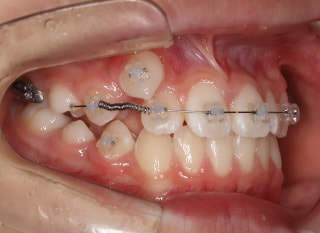

前歯装置装着時